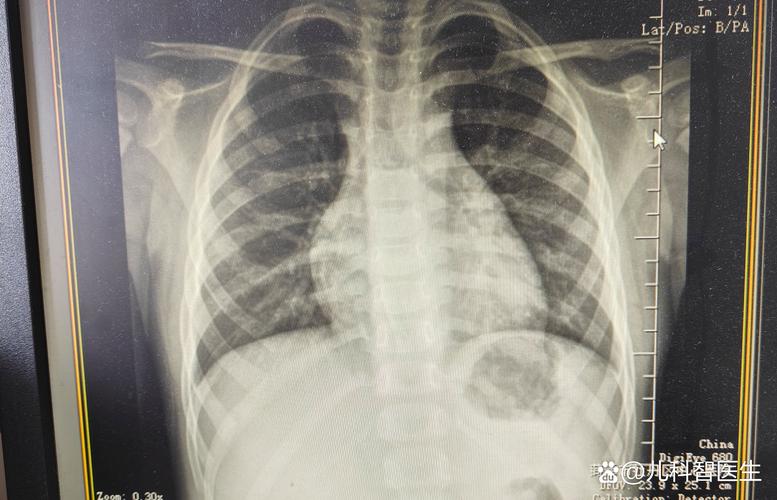

(图片来源网络,侵删)- 这是检测血液中支原体本身的“碎片”或“外壳蛋白”。